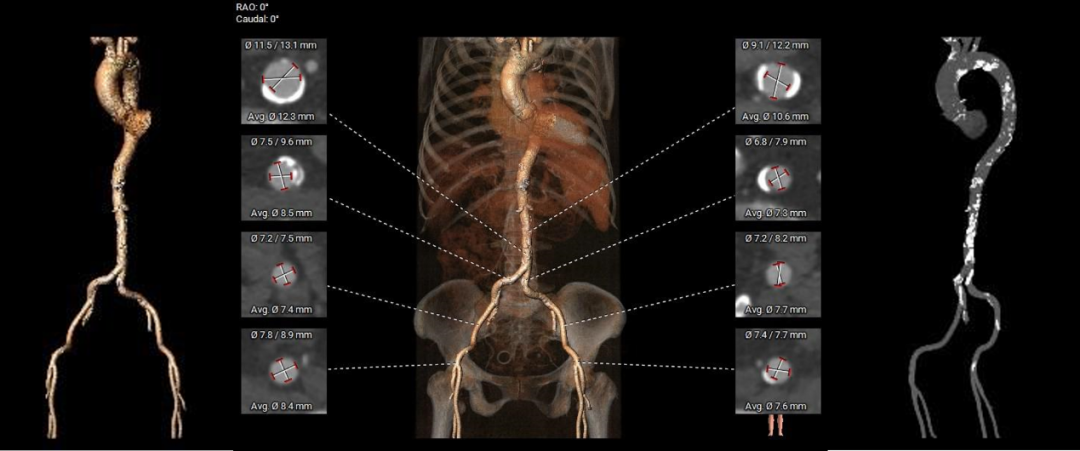

CT动态预览

主动脉根部测量:

CT特点:功能性二叶瓣,瓣叶中度钙化伴增厚,钙化分布不均匀,主要分布于右无交界融合处,且无窦下钙化延伸至LVOT;流入端呈收口形态,瓦氏窦,窦管交界及升主动脉内径可,左右冠脉开口高度可,无冗长瓣叶;非横位心,心室壁肥厚,心腔偏小,双侧髂总动脉分叉前后可见多发钙化斑块,腹主动脉瘤,左髂总动脉有夹层病变。

弓部及入路评估:

入路血管:外周入路走行正常,血管内膜不光滑,双侧髂总动脉分叉前后可见多发钙化斑块,左侧髂总动脉可见夹层。

CT特点:三叶式主动脉瓣,瓣叶轻度钙化伴增厚,钙化分布欠均匀,主要分布于无窦瓣叶边缘及其附着缘,瓦氏窦,窦管交界及升主动脉内径可,左右冠脉开口高度正常,无冗长瓣叶;横位心,心腔内径可,降主动脉及双侧髂总动脉分叉前后钙化严重。

入路血管:外周入路轻度扭曲,血管内膜不光滑,降主动脉及双侧髂总动脉分叉前后钙化严重,血管内径正常。